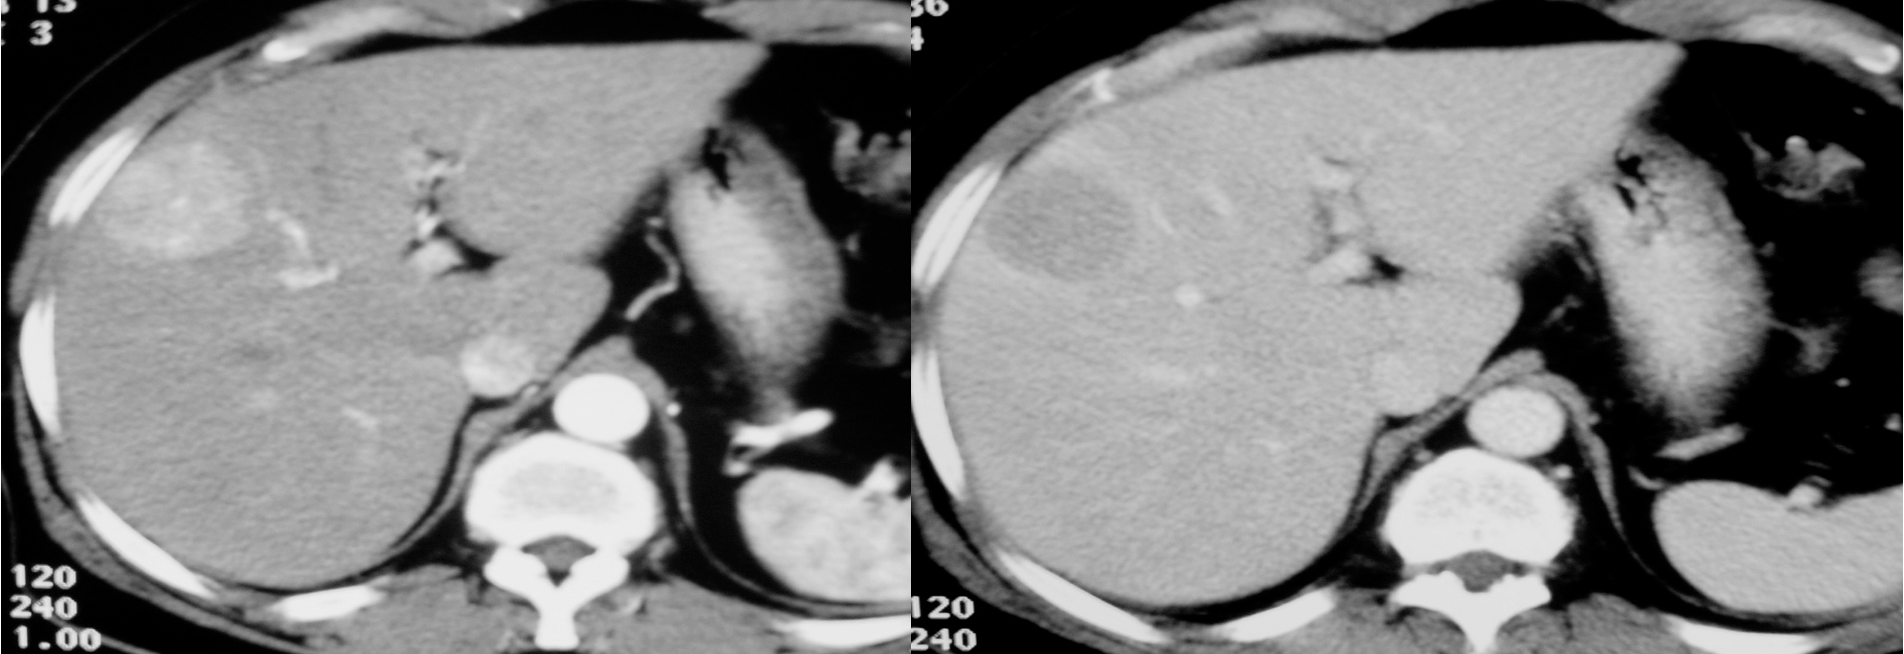

Imaging: Ultrasound, CT scan and MRI can assess the site, size, diagnosis of the tumor and can help in planning the surgical resection. CT scan will show hypervascular tumor.

HCC CT FINDINGS

Arterial phase shows hypervascularity of the HCC tumor on right lobe - washing in

in venous its opposite - washing out

diagnostic for HCC gold standard- doesnt need biopsy

CT scan : Huge hepatocellular carcinoma in the right lobe of the liver

Huge hepatocellular carcinoma in the right lobe of the liver